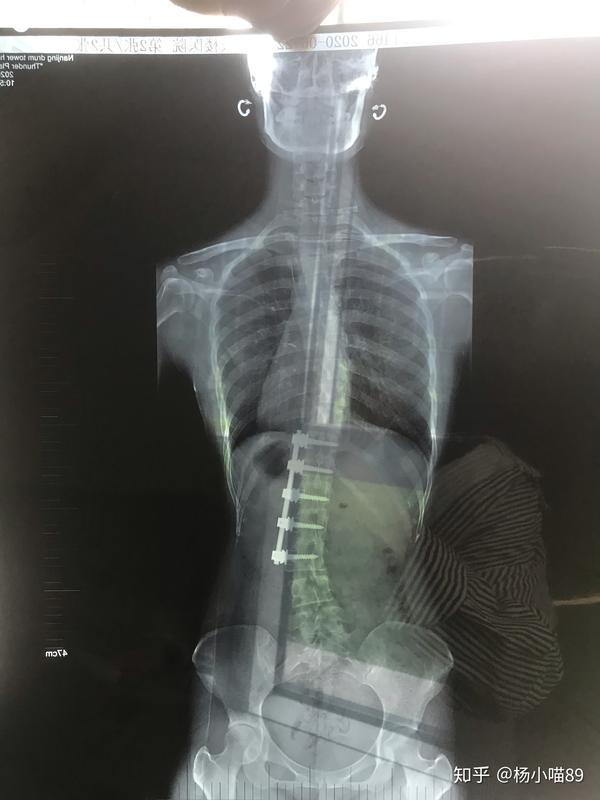

退行性脊柱侧弯ponte截骨矫形术

脊柱侧弯术后1个月复查,效果非常好 (原创)